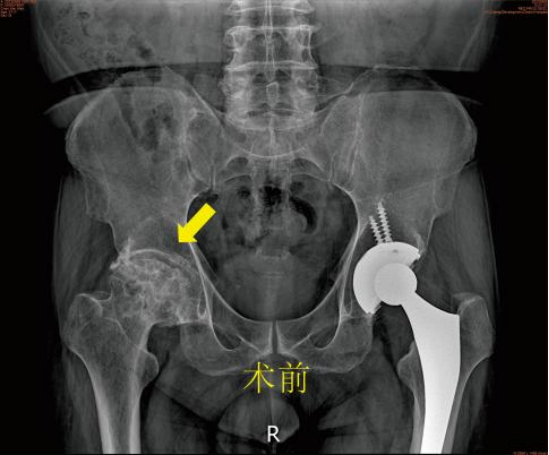

陈先生曾于2015年在某医院住院,当时诊断为双侧股骨头无菌性坏死,做了左侧人工全髋关节置换手术,而右侧则以保守治疗。后来右侧髋关节疼痛逐渐加重,走路一瘸一拐的,严重影响日常的生活质量,更别谈出远门旅行了。这次听亲友建议来到市一医院开发区分院骨科就医。

通过与医生沟通后很快办理了住院手续。骨科接诊医生仔细进行体格检查,完成系统的辅助检查后,全科就患者病情进行讨论决定最终的手术方案为:人工全髋关节置换术。在手术室及麻醉师的协助下,手术顺利的完成。术后第3天患者就可以下地扶助行器行走良好,患者及家属均表示很满意。 九江市第一人民医院开发区分院/朱挺平